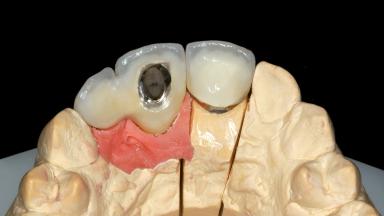

Replacement of an Upper Right Central and Lateral Incisor with an Implant-Supported Crown and a Distal Cantilever

This 20-year-old woman was referred to our department in July 2006. Four months earlier, she had experienced dental trauma to the anterior maxilla when traveling in South America. The emergency treatment included emergency root canal treatment of teeth 12 and 11. Tooth 21 was also subjected to endodontic treatment later. At the initial examination, the patient was not in pain but reported increased mobility of tooth 12. The clinical examination revealed a high smile line, medium thickness of the soft tissue, and rectangular tooth forms. Discoloration of tooth 12 was evident. The periapical radiograph provided by the referring dentist indicated a fracture line at both teeth 12 and 11. A cone-beam computed tomography (CBCT) scan confirmed these fractures. No pathology was found to be associated with tooth 21.